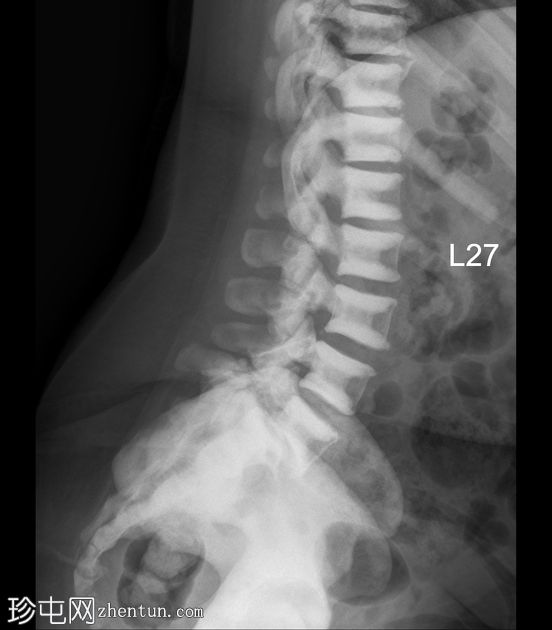

X线片

正位

侧位

弥漫性骨硬化,符合骨硬化症病史。无急性骨折。左髋关节慢性脱位。